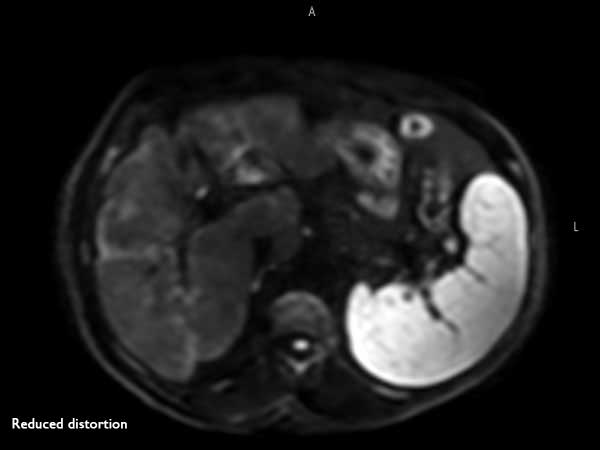

62 year old patient with huge, non-cirrhotic liver tumor. Question is if the portal vein is closed or not which has a direct influence on treatment options. Portal vein turned out to be open and patient was referred for embolization. No other tumors / lesions were found.

Axial T2w TSE